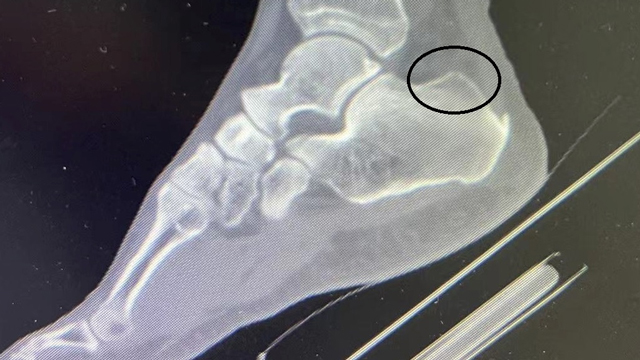

2024年7月,来凤县人民医院骨科率先完成了全县首例踝关节镜手术,目前已开展7例踝关节手术……〔全文〕